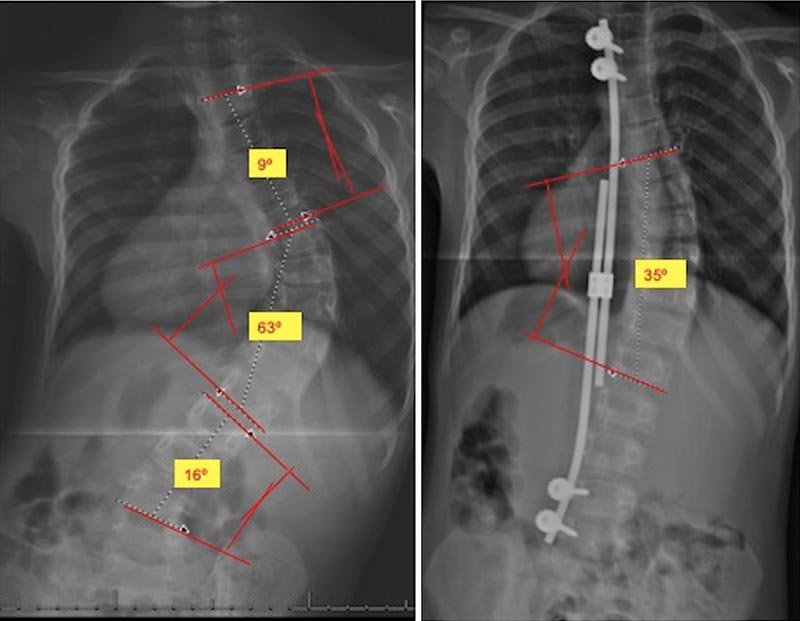

Radiografias são o principal método para o diagnóstico de escoliose congênita e suas mudanças evolutivas durante o seguimento1,6 (exemplo nas figuras 3 e 4). Sempre que possível, as radiografias devem ser feitas com o paciente de pé ou sentado devido a atuação da gravidade na possível acentuação da curva. A severidade das curvas é medida pelo ângulo de Cobb.

Figuras 3 e 4. Exemplos radiográficos demonstrando achados de escoliose congênita